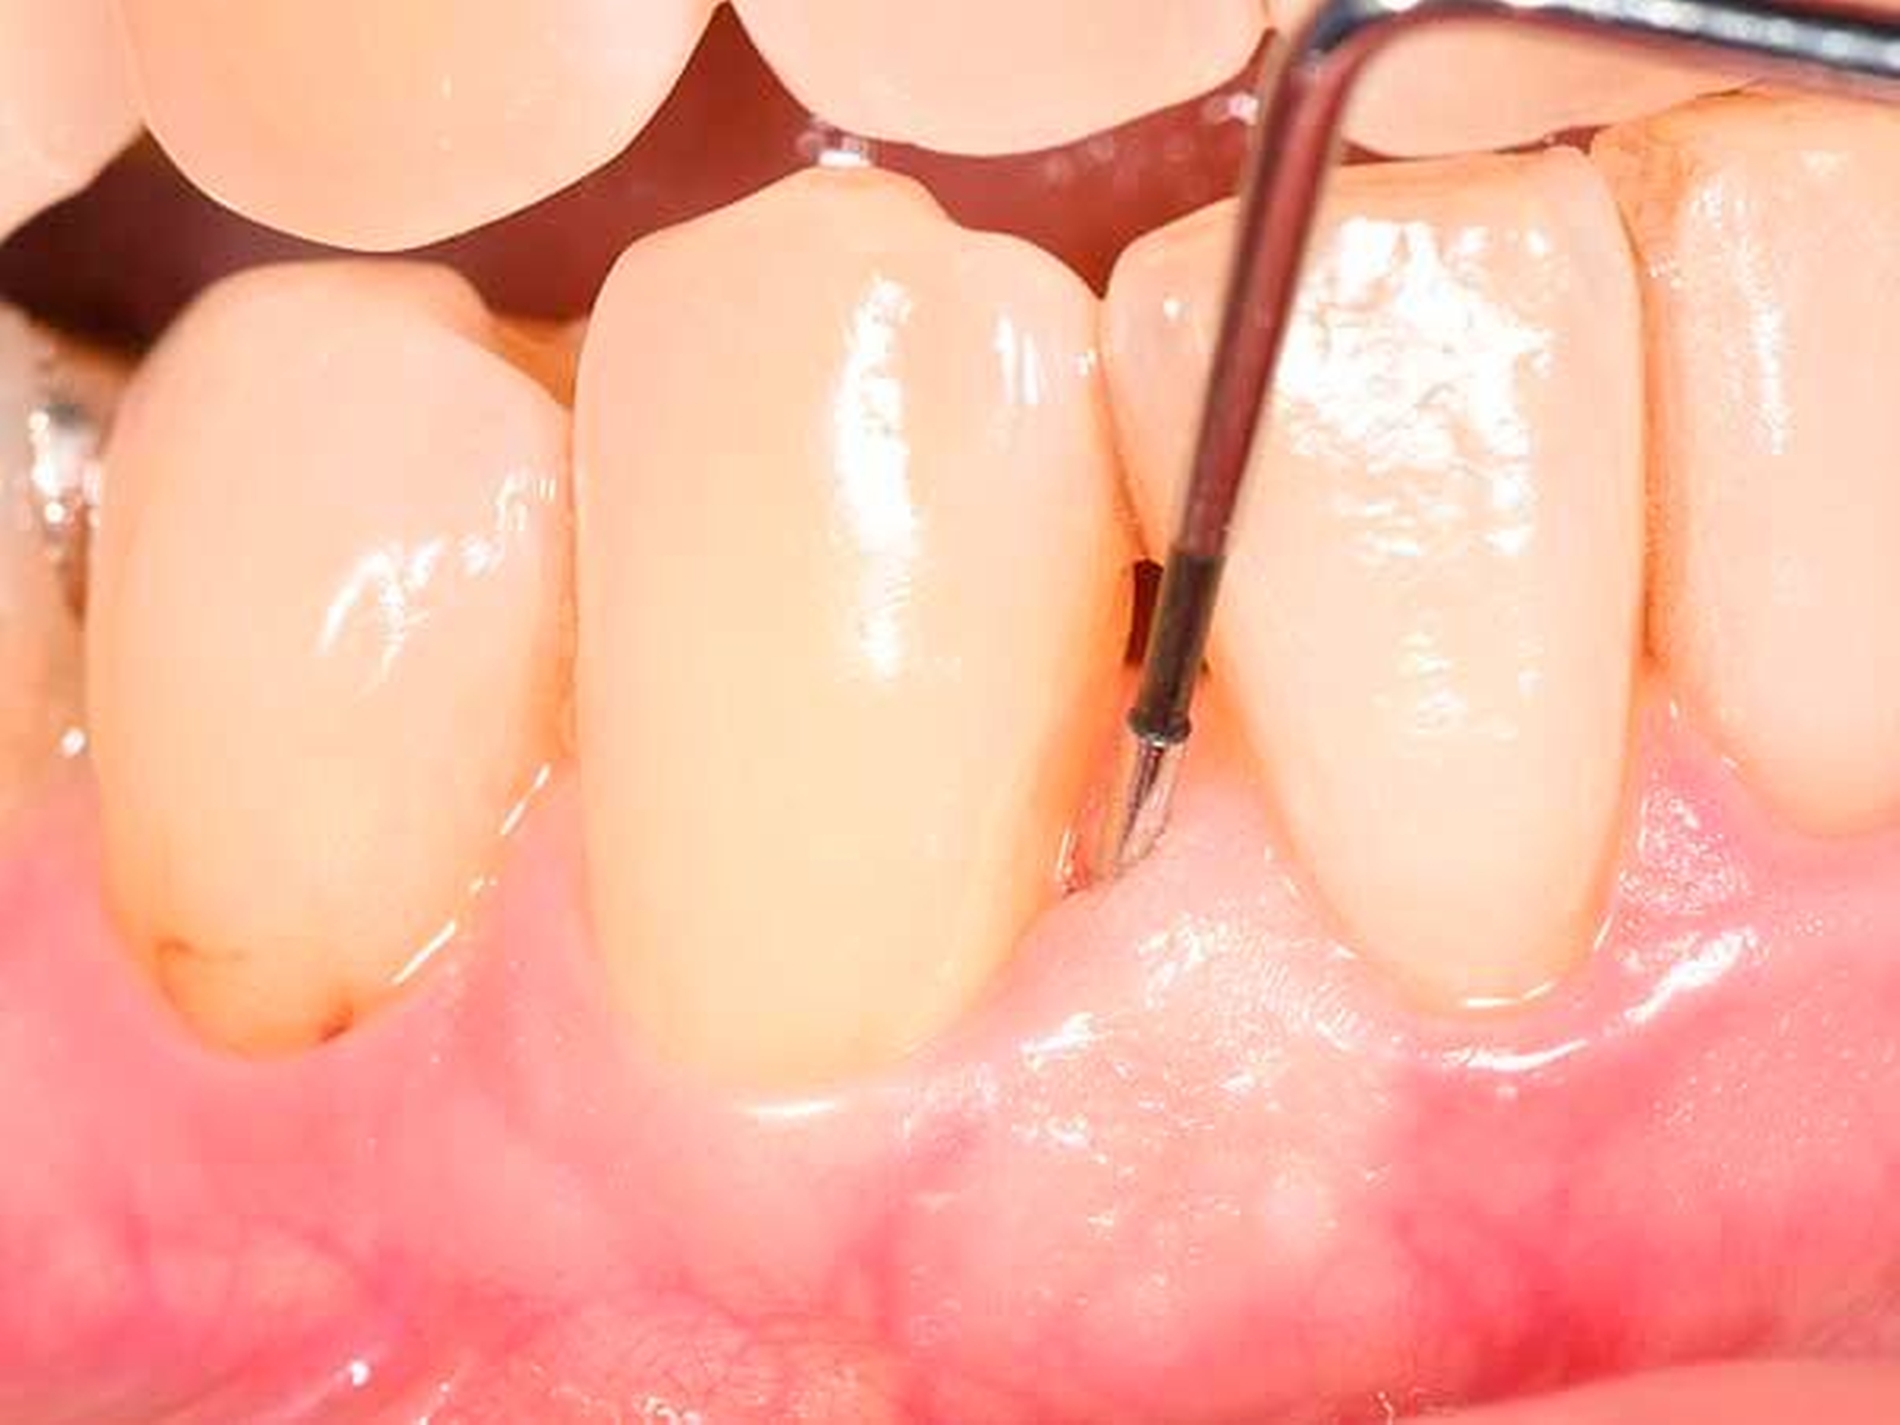

Es ist nachvollziehbar, dass eine solche Modifizierung der parodontalen Wundheilung nur Berücksichtigung von systemischen und lokalen Patientenfaktoren sowie einer optimalen chirurgischen Technik funktionieren kann. Als wesentlich hat sich auf Ebene der Patientenfaktoren herausgestellt, dass regenerative Eingriffe bei Patienten mit Vorliegen von Verhaltensfaktoren wie Rauchen oder mangelnder Compliance sowie von systemischen Faktoren wie einem schlecht eingestellten Diabetes mellitus oder einer hohen Stressbelastung mit einem deutlich erhöhten Misserfolgsrisiko vergesellschaftet sind. Auf lokaler Ebene ist zu fordern, dass der zu regenerierende Defekt eine möglichst große Tiefe sowie einen möglichst geringen Defektwinkel aufweisen sollte (Abbildung 6a). Mehr als die Hälfte der Variabilität eines regenerativen parodontalchirurgischen Eingriffs konnte in einer klassischen Studie auf die Kombination der Faktoren Defekttiefe und Defektwinkel zurückgeführt werden [Tonetti et al., 1996]. In einer deutschen Studie wurde erst bei Defekten einer intraossären Tiefe von 3 mm oder mehr sowie eines Defektwinkels von 25° und weniger ein deutlicher Attachmentgewinn nachgewiesen [Klein et al., 2001]. Zusätzlich erfordert ein regenerativer Eingriff optimierte Weichgewebeverhältnisse (Abbildung 6b) – die Zahl von parodontalpathogenen Bakterien des roten Komplexes ist direkt mit einer verschlechterten OP-Prognose assoziiert [Heitz-Mayfield et al., 2006], und die Möglichkeit eines primären Verschlusses der Lappen ist ein wesentlicher Faktor für den Erfolg des regenerativen Eingriffs [Cortellini und Tonetti, 2015]. Zur Sicherstellung der primären Deckung des OP-Gebiets sind verschiedene papillenerhaltende Lappentechniken beschrieben worden. Häufig werden in Abhängigkeit von der Breite der Interdentalpapille der modifizierte (Abbildung 7a bei dreiwändigen Defekten wie in Abbildung 7b; Abbildung 7c bei ein- oder zweiwändigen Defekten wie in Abbildung 7 d) oder der vereinfachte Papillenerhaltungslappen (Abbildungen 7e und 7f) angewendet.